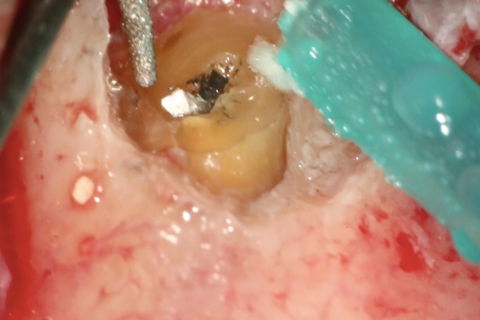

Remoção Microcirúrgica do Cone de Prata

Remoção Cirúrgica do Cone de Prata

Após o retratamento endodôntico convencional, o paciente foi submetido a uma microcirurgia apical. A osteotomia e apicectomia foram feitas com o uso de uma ponta ultrassônica (W1-CVDentus-Brasil). O fragmento apical do cone de prata tornou-se visível em uma ampliação de 12,5x (Figura 6). A fim de remover o fragmento apical, uma Ponta Ultrassônica P1M (Helse Ultrasonic - Brasil) foi usada (Figura 7, Figura 8). Após a remoção microcirúrgica do cone de prata, a preparação retrógrada foi realizada com a mesma ponta ultrassônica (Figura 9).